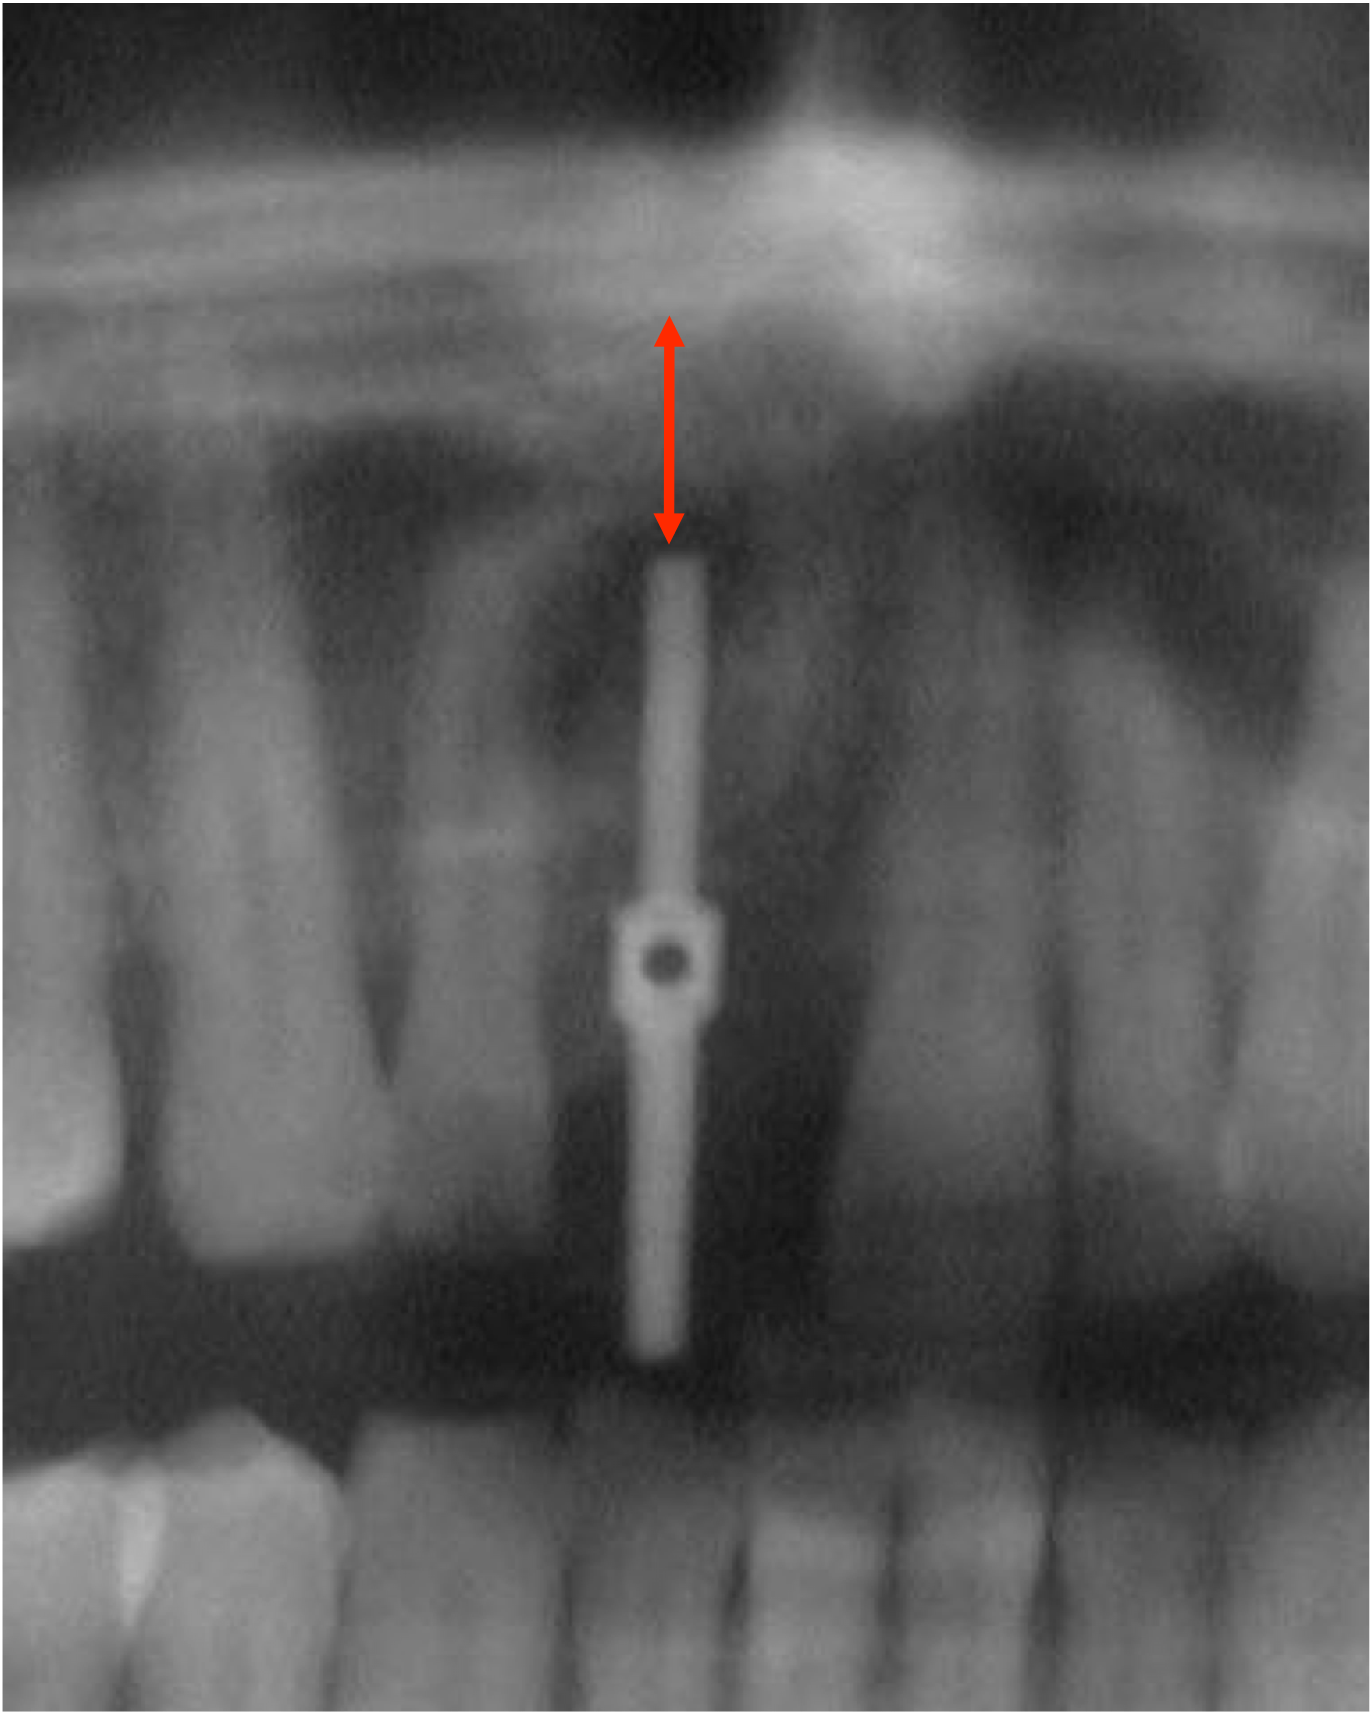

Fig 4. Radiographic imaging was used to establish vertical control of implant placement and ensure the presence of sufficient bone on either side of the implant.

Figure 4

Fig 9. An enlarged panorex image with the direction-indicating pin in place was used to plan proper implant placement depth, particularly in the context of the exact height of bone.

Figure 9

Radiographic examination of the site for implant placement is essential to determine the presence of adequate space for the implant and subsequent restoration (eg, central incisor) and to assess soft-tissue architecture.1,2 Computed tomography (CT) images and panoramic radiographs (eg, panorex) have been used in implant dentistry to help identify structures critical for implant placement and establish the safe, short distance for implant placement (ie, vertical control of implant placement) using a pilot drill (Figure 4).5

Pilot drills, which are typically 2 mm wide, are used to drill into the trajectory of the bone to a short, safe distance to establish position and angulation (Figure 7). Care must be taken to observe the premaxilla angulation, which averages 20 degrees. Then, a direction-indicating pin is placed (Figure 8) and a radiographic image is taken (Figure 9).7 This image (eg, panorex) is enlarged to enable further analysis and measurements, particularly to establish the exact height of bone.

The approximate 20% horizontal and vertical distortion is calculated.4 This can be accomplished by measuring from the top of the guide pin to the opposing vital structure (eg, floor of the nose, 5 mm). Because of the 20% distortion, the actual measurement is 4 mm. Thus, there is a total of 14 mm of vertical bone height (ie, 10 mm for the length of the pin, plus 4 mm to the floor of the nose), and a 13-mm-length implant would be selected.